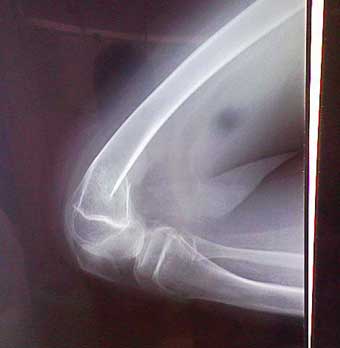

「アグーナリー中に和馬が骨折して神戸の病院に搬送されました」とのこと。

もうすでに応急措置は終わっており、ギプスもまかれていました。主治医の宇多野病院へという紹介状とフィルムをもって一路京都へ。ボーイスカウト日本連盟が用意していたリフト付きウェルキャブ車を自ら運転して帰りました。

ちょうど半年前1月に全く同じ箇所の反対の足(右足)を骨折していたので、だいたい様子はわかります。宇多野へは月曜日に行くことにして痛み止めの座薬をもらいました。

こんな感じです。 これからまた1カ月! 今度は真夏なのでたいへん! |